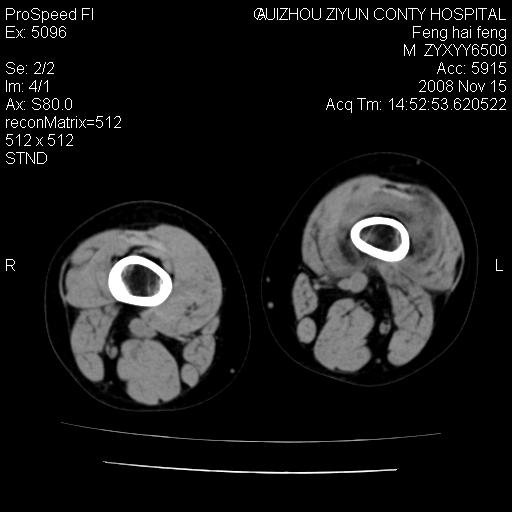

标题: CT16656:M 14Y 左膝关节肿胀一年余。其余病史不详。 [打印本页]

标题: CT16656:M 14Y 左膝关节肿胀一年余。其余病史不详。

考虑左侧髌骨结核;左膝关节滑膜肿胀、增厚,关节囊积液。

左膝滑膜型关节结核可能性大!支持!滑膜型关节结核主要ct表现:关节囊肿胀,积液,关节面见小破坏灶,并见点状死骨!

好大的左腿!考虑左侧髌骨结核,左膝关节滑膜肿胀、增厚,关节囊积液。

左侧髌骨结核;左膝关节滑膜肿胀、增厚,关节囊积液